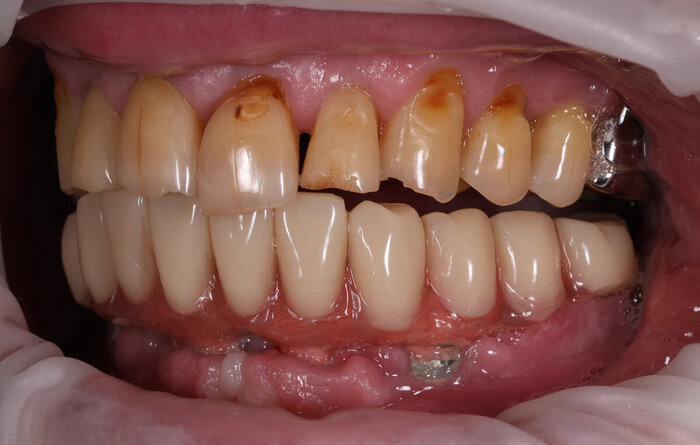

Делаем фото до:

И во рту:

До.

До имплантации.